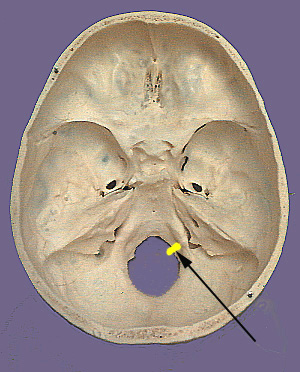

Cranium CN XII

CN XII. Hypoglossal Nerve

The hypoglossal nerve as the name indicates can be found below the tongue. It is a somatomotor nerve that innervates all the intrinsic and all but one of the extrinsic muscles of the tongue. The neuronal cell bodies that originate the hypoglossal nerve are found in the dorsal medulla of the brain stem in the hypoglossal nucleus. This nucleus gives rise to axons that exit as rootlets that emerge in the ventrolateral sulcus of the medulla between the olive and pyramid. The rootlets come together to form the hypoglossal nerve and exit the cranium via the hypoglossal canal. The nerve passes laterally and inferiorly between the internal carotid artery and internal jugular vein. The twelfth cranial nerve travels lateral to the bifurcation of the common carotid and loops anteriorly above the greater horn of the hyoid bone to run on the lateral surface of the hyoglossus muscle. It then travels above the edge of the mylohyoid muscle. The hypoglossal nerve then separates into branches that supply the intrinsic muscles and three of the four extrinsic muscles of the tongue.